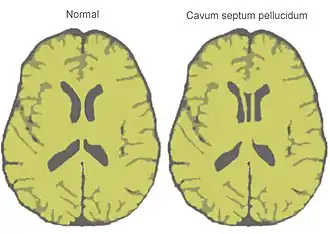

Normal brain and cave of septum pellucidum as shown on a stylized horizontal section through the brain | |

The cave of septum pellucidum (CSP), cavum septi pellucidi, or cavity of septum pellucidum is a slit-like space in the septum pellucidum that is present in fetuses but usually fuses during infancy. The septum pellucidum is a thin, laminated translucent vertical membrane in the midline of the brain separating the anterior horns of the right and left lateral ventricles. It lies posterior to the corpus callosum. Persistence of the cave of septum pellucidum after infancy has been loosely associated with neural maldevelopment and several mental disorders that correlate with decreased brain tissue.[1][2][3][4][5]

There are individual differences in the degree of CSP; whereas some have complete closure of the cavum, others present with a small degree (4–6 mm wide, in the coronal plane) of incomplete closure.[4] The most common type of CSP is noncommunicating; that is, it does not connect to the brain's ventricular system. Because of this lack of communication, the previous use of the term "fifth ventricle" is no longer used, and the fifth ventricle is the name often used for the terminal ventricle.